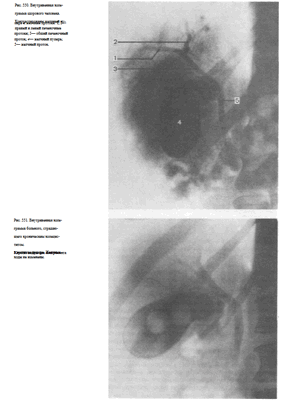

Выделительная холеграфия (холецистохолангиография) осуществляется путем внутривенного введения 20—40 мл 50—70% трийодированного контрастного вещества. Эта методика позволяет изучить состояние не только желчного пузыря, но и желчных ходов. Желчные протоки оптимально контрастируются в течение первых 30 мин, а желчный пузырь — через 1 '/г ч.

При выделительной холецистохолангиографии на снимках отчетливо видны печеночные протоки, общий желчный проток, пузырный проток, а также желчный пузырь (рис. 550). Интенсивность выделения препарата печенью характеризует и ее выделительную функцию.

Усиление интенсивности тени контрастной желчи, перемешивание ее с оставшейся в пузырене контрастной желчью, свидетельствует о хорошей концентрационной способности пузыря. Последующий прием внутрь яичного желтка (яйца) позволяет изучить функцию сфинктера Одди, а также двигательную способность желчного пузыря.

Выделительная холеграфия дает возможность выявить холестериновые камни как желчного пузыря, так и расположенных в желчных протоках, а также исследовать желчные пути после холецистэктомии (рис. 551).

Для изучения состояния общего желчного и печеночных протоков применяют интраоперационную холангиографию. При этом хирург вводит водорастворимое контрастное вещество непосредственно в желчные пути посредством пункции. Чаще всего пунктируют пузырный или общий желчный проток в терминальном отделе. После измерения давления в желчных путях из них отсасывают некоторое количество содержимого и осторожно, под небольшим давлением, вводят 10—20 мл контрастного вещества.

Не удаляя иглы с помощью переносного или палатного аппарата производят рентгеновский снимок (кассету подкладывают под больного заранее) и подвергают его срочной фотообработке. Перед рентгенографией хирургические инструменты стремятся расположить вне проекции желчных путей (рис. 552).